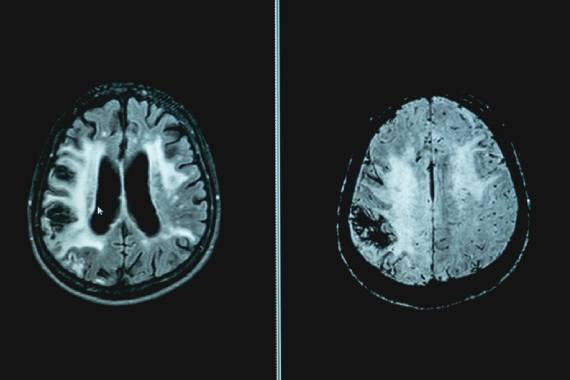

Vascular dementia is the second most common type of dementia, affecting around 150,000 people in the UK. There is no cure, but we fund research that could change that.